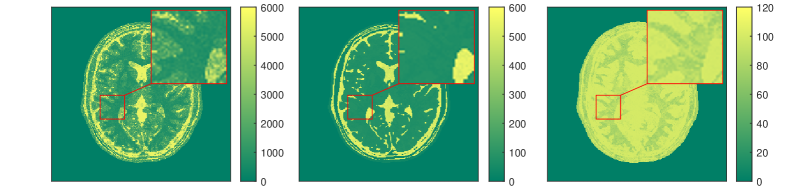

We present some numerical examples in Figure 12, where we compute solutions of the optimization problem (3.36). In this example, the neural network simulating the Bloch map is trained via a training set which was obtained through discrete dynamics of simulated Bloch data. In particular, a set of parameter pairs in the feasible domain of and is taken as inputs of the network, and then the simulated Bloch dynamics resulting from all these pairs are regarded as the outputs. The simulated k-space data in this example are generated using exactly the same setting as the one used for Figures 3 and 4. For such a discrete time series, the Bloch map is a Nemytskii type operator, and thus can be approximated sufficiently well in a uniformly bounded feasible set.